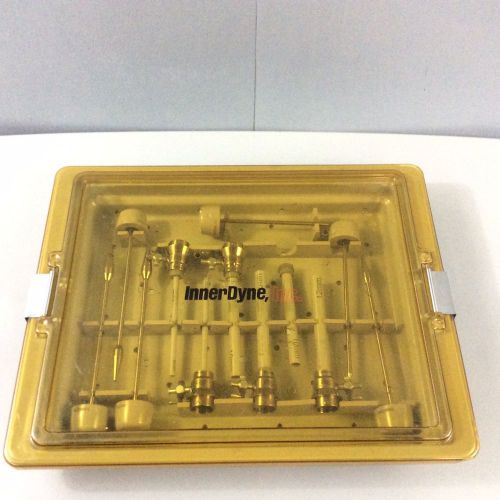

InnerDyne Trocar & Cannula Set